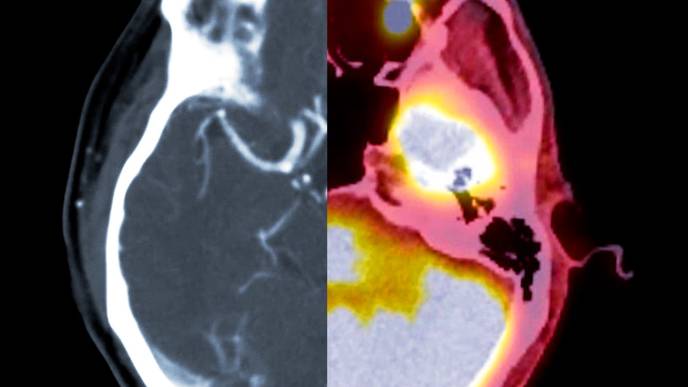

Participants who were eligible based on blood tests also underwent positron emission tomography (PET) scans, brain scans that are used to directly measure amyloid buildup in the brain. Among “plasma eligible” participants (those who met the blood test cutoff), individuals from all racial and ethnic groups were equally likely to be eligible to participate based on PET scan data. The study was just published in Alzheimer’s & Dementia: The Journal of the Alzheimer’s Association.

The researchers collected blood from each participant and calculated amyloid levels, using a liberal threshold to determine who was considered eligible for inclusion in the clinical trial. The trial requires a participant to have 20 centiloids or more of amyloid, but researchers lowered the cutoff to 11 centiloids to avoid excluding participants who might be just below the typical threshold. Centiloids are units in a standardized method of measuring amyloid plaque in the brain based on PET imaging.